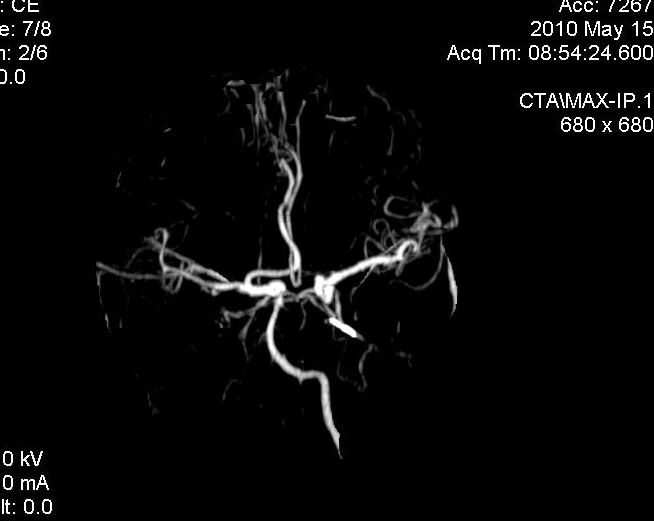

男.60岁,渐进性意识不清,ct检查双侧额颞顶部硬膜下血肿,开颅术后行脑血管cta,大脑中动脉起始部见一瘤状血管扩张。请各位老师留下宝贵意见

太常见了,报动脉瘤就可以

符合动脉瘤表现。

符合动脉瘤表现。

动脉瘤。

颅内动脉瘤。

后重建做得不是很好看,要将维蒂斯环充分显示,最好在增加一个mip。这样不好定位。

小动脉瘤

典型

符合动脉瘤的表现

动脉瘤

符合动脉瘤表现。

小动脉瘤

典型